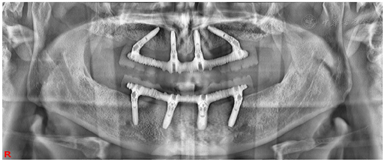

治疗过程(1)手术方案设计:拔除余留牙后,上颌拟在12、22植入2颗轴向植体,15、25植入2颗倾斜植体,下颌于32、42植入2颗轴向植体,35、45区域植入2颗倾斜植体,种植体倾斜角度小于45°,术后制作临时种植固定义齿,6月后戴终义齿(钛支架加丙烯酸树脂材料)。(2)种植一期术前测量垂直距离。术中拔除上下颌余留牙,分别于16-26、36-46区牙槽嵴顶近远中向切开牙龈黏膜,翻瓣,搔刮拔牙窝内炎性肉芽组织,平整牙槽嵴顶骨嵴,分别于12、15、22、25、32、35、42、45区定点,逐级备洞,12、22、32、42区轴向植入Nobel Speedy 4x13mm种植体,15、25、35、45区远中倾斜植入Nobel Speedy 4x15mm种植体。初期稳定性均达到35N·CM。15、25放置RP 5 mm 30°复合基台,12、22放置RP 3 mm 17°复合基台。32、42放置RP 2 mm 0°复合基台,35、45放置RP 4mm 30°复合基台,放置愈合帽,修整牙龈黏膜,缝合牙龈(图4)。术后拍摄全景片(图5)(3)即刻负重制取上下颌印模,制作蜡堤记录上下颌颌位关系,采用息止颌位法确定垂直距离,吞咽咬合法确定水平关系,转移颌位关系后,手术当日制作临时固定义齿修复至第二前磨牙并戴入固定,调整咬合接触(图6)。

术后复查:术后3月全景片显示种植体骨结合良好(图7)。制作终义齿:术后5月:取下临时固定义齿,制取上下颌硅橡胶印模,根据临时义齿,记录上下颌颌位关系,上牙合架。术后6个月:制作义齿蜡型、排牙(图8),取下临时固定义齿,口内试戴上下颌终义齿蜡型,检查咬合关系良好,上下颌中线居中、对称,露齿线、唇颊面部丰满度患者满意。术后6个月:取下临时义齿,戴入终义齿,修复至第一磨牙(图9)。随访术后1年:全景片显示种植体周围骨结合良好,上前牙区种植体颈部骨吸收约1 mm(图10)。术后2年:义齿外形无变化,组织面有菌斑沉积。治疗计划:1.患者口腔卫生宣教,指导正确刷牙,采用冲牙器冲洗义齿与牙龈间缝隙,要求定期(6个月)复查、维护。2.取下上下颌义齿,复合基台周围洁治,清洁义齿,抛光义齿组织面,重新戴入固定上下颌义齿(图11)。术后2年全景片:种植修复前后面像对比(图13)。